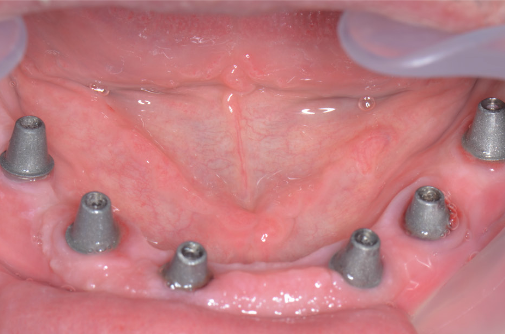

Pe baza scanărilor imagistice 3D (CBCT) se vor efectua măsurători ale înălțimii și lățimii osului mandibular, astfel încât medicul implantolog să poată decide dacă se pot insera implanturi direct sau este nevoie de adăugare de os în prealabil. Se realizează un ghid chirurgical care ajută la poziționarea precisă a implanturilor în os (Fig.3.6.4. dr. Ondine Lucaciu), iar în 24 de ore după această intervenție pacientul primește o punte provizorie fixă pe care o va purta un interval de 3-6 luni, perioadă necesară osteointegrării implanturilor, respectiv vindecării (Fig. 3.6.5). Această lucrare provizorie va fi înșurubată în 6 puncte, în cele 6 implanturi inserate în mandibulă (Fig. 3.6.6).

După acest interval lucrarea provizorie se îndepărtează, în fiecare implant se montează câte un dispozitiv necesar realizării amprentelor (Fig. 3.6.7) care vor servi tehnicianului dentar pentru realizarea punții definitive (Fig. 3.6.8 și Fig. 3.6.9). Realizarea acesteia se face în câteva zile, interval în care pacientul va continua să poarte lucrarea provizorie realizată inițial.